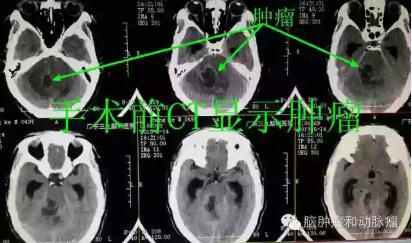

▲手术前CT显示肿瘤位置,但是不能确诊,需要进一步检查